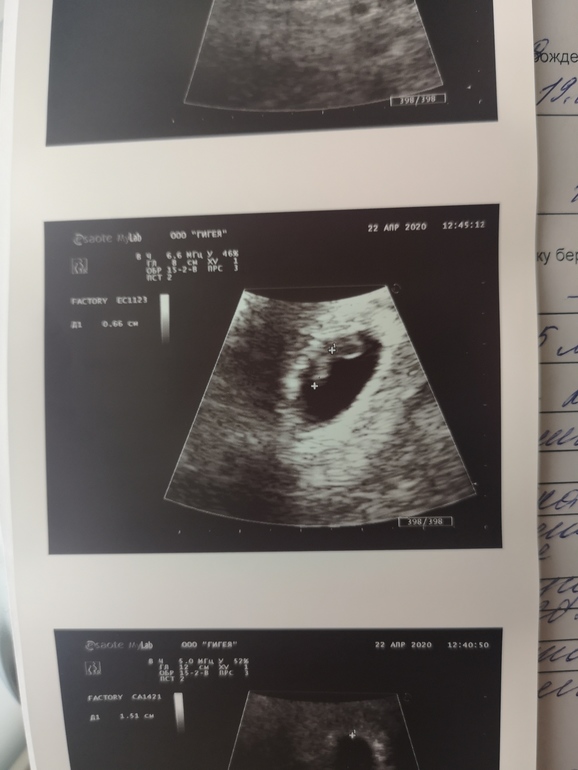

Здравствуйте мамочки и и девушки в ожидании! Мне 29, первая беременность! Столько вопросов и переживаний, что аж дурно становится))) В общем предупреждаю, будет много букофф) Пдпм был 19 февраля, цикл не стабильный, по этому на 63 день цикла (22 апреля) только решила сделать тесть, так как предшествующие пару недель была вялость, ночью мутило, пропал аппетит, тянущие ощущения внизу живота (не боль, а как будто растягивается матка, как перед месячными) . Тест сделала, что бы отмести или подтвердить положение. 2 полоски!!! Долгожданные!!! Утром полетелела делать УЗИ и сдать кровь на хгч. По данным УЗИ (фото заключения), по хгч - 22652. Вот по сроку мне не понятно. Узист сказала, все соответствует сроку 47 дней. Но геникологи же считают акушерский срок от пдпм, то есть 9 недель по моим данным? Или я что то путаю? Может кто сможет пояснить? И как часто сдавать кровь на хгч и нужно ли это? Первый скрининг где то через 1-1,5 месяца, это так долго 😬 понимаю, что лучше успокоиться, организм сам знает, как справляться. Но блин, я переживаю, что что то может пойти не так, а я вовремя не обнаружу проблему. Так что всем заранее спасибо за участие 🙂Valeriya

Добрый день. Такая же ситуация с нестабильным циклом. В ЖК будут считать так, как на узи увидели, т.е. в вашем случае 6 нед 5 дней. Потом по тому, что на узи скрининга поставят. Так что ориентируйтесь на узи. Мне на скрининге сказали на вопрос о последнем дне месячных сразу говорить, что цикл не стабильный и говорить срок по узи, чтобы не путать никого.

ПДР и срок будут уточнять на основании первого скрининга, если расхождения будут с последними месячными более, чем на неделю. Пока вкусно и правильно кушайте, витамины с врачом обсудите, сами только не назначайте себе ничего. Если уже пили фолиевую - не отменяйте пока. Уже можете записаться на консультацию к врачу, на УЗИ тем более увидели и малыша, и СБ. Врач направит на анализы и всё расскажет. Лёгкой беременности!